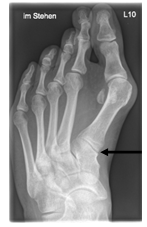

Der Fuß ist mit seinen knapp dreißig Gelenken und Muskeln eine komplexe anatomische Konstruktion, die im Alltag einer großen Belastung ausgesetzt ist. Eine Vielzahl von möglichen Fehlstellungen erfordert vom behandelnden Arzt große Erfahrung, um die Beschwerden beim Gehen, Stehen oder Sporttreiben der richtigen Ursache zuordnen zu können. Die häufigste Fehlstellung am Fuß ist der Zehenballen (Hallx valgus). Allein in Deutschland sind 10 Mio. Menschen betroffen, davon jeder Dritte bei über 65-Jährigen. Schmerzen vor allem an der Innenseite der Großzehe können das Gehen beschwerlich machen. Manchmal kommt es im Verlauf zur Verdrängung der daneben liegenden Zehe (Krallenzeh). Auch kann es durch Fehlbelastung zu Schmerzen unter der Fußsohle kommen.

Wenn die Beschwerden über einen längeren Zeitraum bestehen und durch angepasstes Schuhwerk nicht abklingen, kann eine operative Korrektur erfolgen. Ziel ist hierbei die Begradigung der Zehe(n), um die Belastbarkeit wieder herzustellen. Es gibt hierfür viele verschiedene operative Optionen mit unterschiedlichen Vor- und Nachteilen. Die Wahl des richtigen Operationsverfahrens erfordert vom behandelnden Arzt Fingerspitzengefühl und Erfahrung und ist für den langfristigen Verlauf entscheidend. Nachfolgend werden wesentliche Informationen hierzu aufgeführt.

Begradigung durch Knochenverschiebung

Hierbei wird der Mittelfußknochen nach außen verschoben und mit zwei kleinen Schräubchen wieder befestigt (Osteotomie nach Chevron). Ebenfalls wird ein verkürzter Muskel gelöst, damit der Zeh in gerader Position verbleibt (sog. laterales Release). Sollte die Fehlstellung auch innerhalb der Zehe vorliegen, wird auch ein kleiner Keil am Großzehengrundglied entnommen (Osteotomie nach Akin).

Auf dem Röntgenbild zeigt sich die fortgeschrittene Arthrose des Großzehengrundgelenkes. Der Knorpel ist vollkommen zerstört (Pfeil). Es reibt Knochen auf Knochen, was die Schmerzen verursacht.